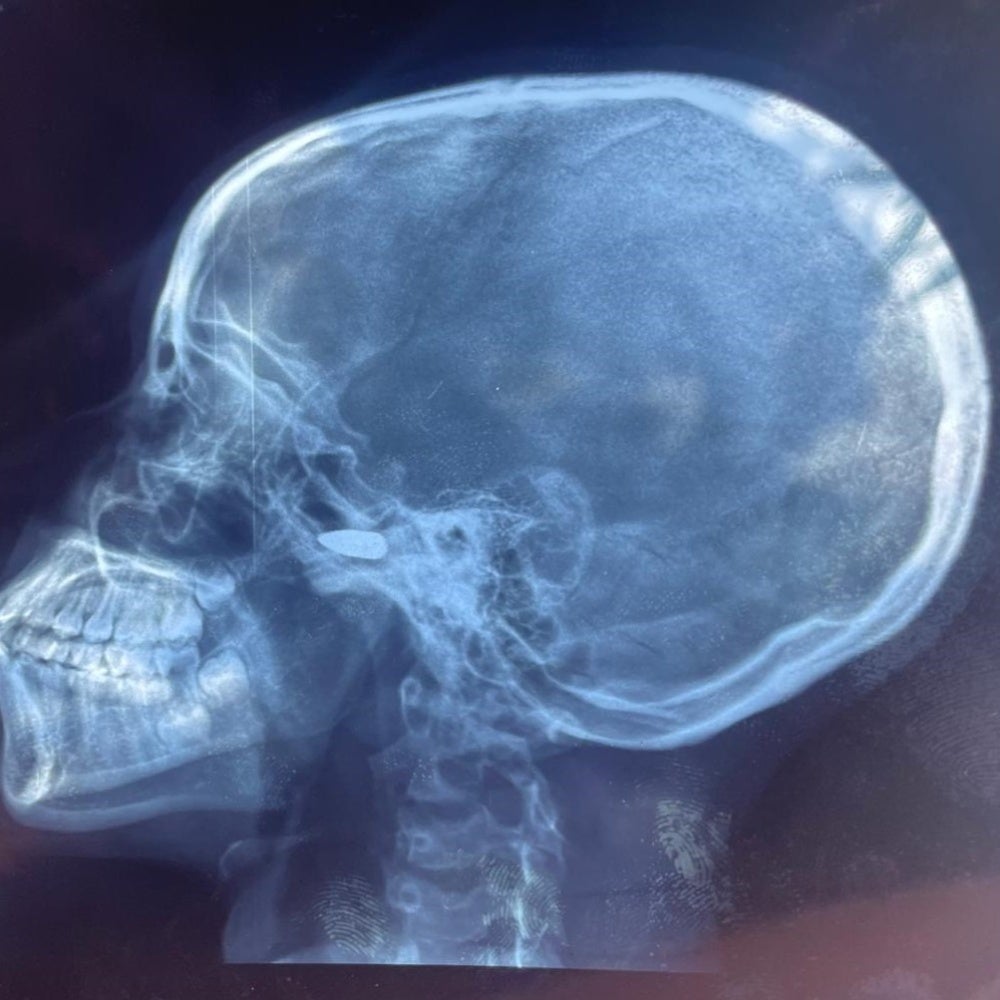

The organizations saw x-rays from six people who had bullets lodged in their bodies. Three of the people had not yet had the bullets removed at the time of interview in August.

A 15-year-old girl from Bebedjia, a town in Logone Oriental province, said:

I went into my room because of the shooting. After a few minutes a bullet came through the roof and hit me on the head. It was bleeding a lot … The bullet is still in my head and the doctors say we have to wait. It makes me very scared.